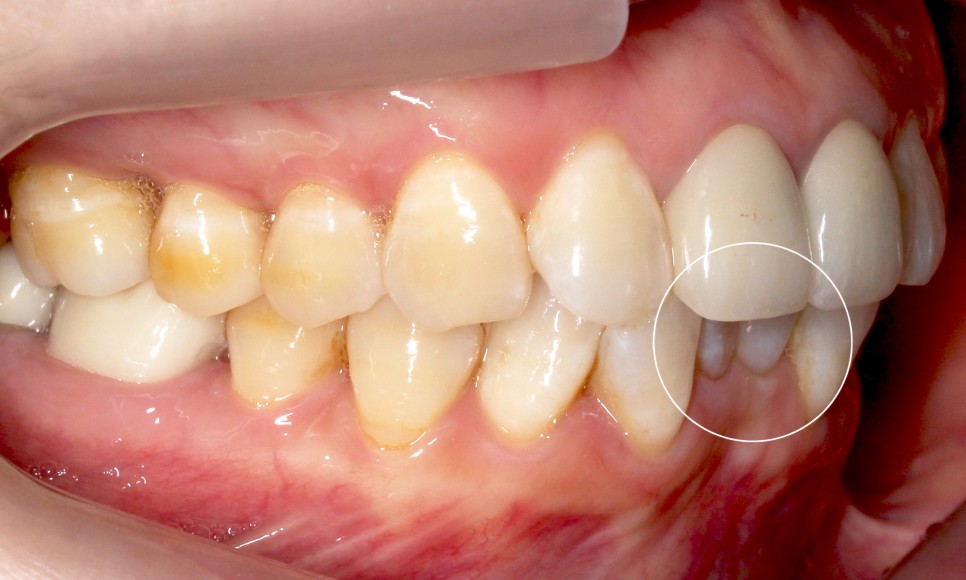

반대쪽으로 보아도

같은 모습을 확인할 수 있는데요.

이렇게 아랫니가 윗니를 향해

깊숙히 물린다면

아랫니의 절단연에 의해

윗니의 잇몸이 상처 입을 수 있습니다.